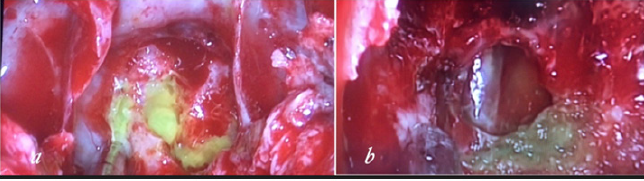

Before surgery, a lumbar puncture was performed to administer 0.25 mL of 10% fluorescein with 10mL of cerebrospinal fluid (CSF) to help visualize CSF leaks during surgery and to ensure there was no leak after reconstruction of the defect. The patient underwent endoscopic trans nasal transsphenoidal surgery. The anterior and middle portions of the clivus were exposed between both carotid arteries. During surgery, the defect was defined to the left of the midline in the clivus. The basilar artery was seen through the defect in prepontine cistern (Figure 2). The defect was closed with a multilayer reconstruction consisting of fat, fasciculata and naso septal flap (Figure 3). There was no recurrence of CSF leak at 2 years follow-up.

Figure 2: (a) intraoperative endoscopic view show csf leakage from clivus defect just inferior to sella.

(b) basilar artery in prepontine cistern behind the defect